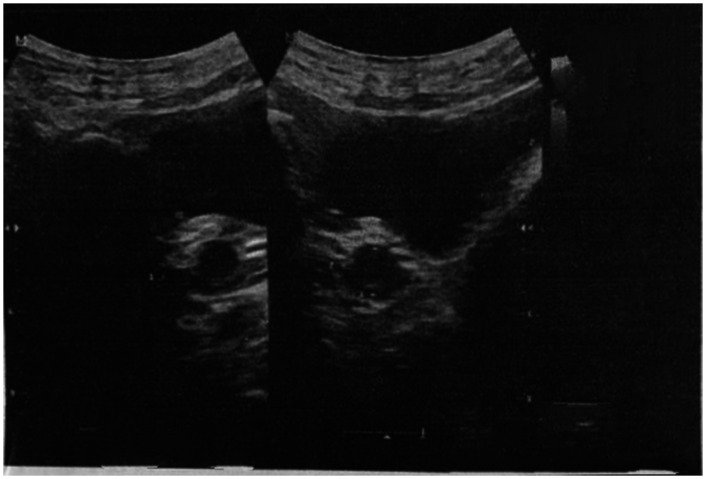

Swyer综合征是一种完全性腺发育不良的形式,是一种罕见的遗传病,其表型女性表现为46,xy核型。15岁女孩,第二性征发育不全,闭经。实验室检查显示促卵泡激素水平升高,雌二醇水平低,同时影像学检查发现子宫和性腺小。染色体分析证实为46,xy核型。患者接受激素替代治疗,青春期发育明显,8个月内达到Tanner期3。这个病例强调了早期识别,染色体分析和量身定制的管理在斯威耶综合征的重要性。基于激素治疗、生育咨询和心理支持的多学科方法对改善患者预后至关重要。作为叙利亚首例Swyer综合征病例报告,本研究强调需要提高对这种罕见疾病的临床认识,并扩大原发性闭经的鉴别诊断。

Swyer syndrome, a form of complete gonadal dysgenesis, is a rare genetic condition in which phenotypic females exhibit a 46,XY karyotype. A 15-year-old girl presented with underdeveloped secondary sexual characteristics and amenorrhea. Laboratory investigations revealed elevated follicle-stimulating hormone levels and low estradiol levels, while imaging identified a small uterus and gonads. Chromosomal analysis confirmed a 46,XY karyotype. The patient was treated with hormone replacement therapy, resulting in significant pubertal development, reaching Tanner stage 3 within 8 months. This case highlights the importance of early recognition, chromosomal analysis, and tailored management in Swyer syndrome. Multidisciplinary approaches based on hormonal therapy, fertility counseling, and psychological support are crucial to improving patient outcomes. As the first case report of Swyer syndrome in Syria, this study underscores the need for heightened clinical awareness of this rare condition and widens the differential diagnosis for primary amenorrhea.